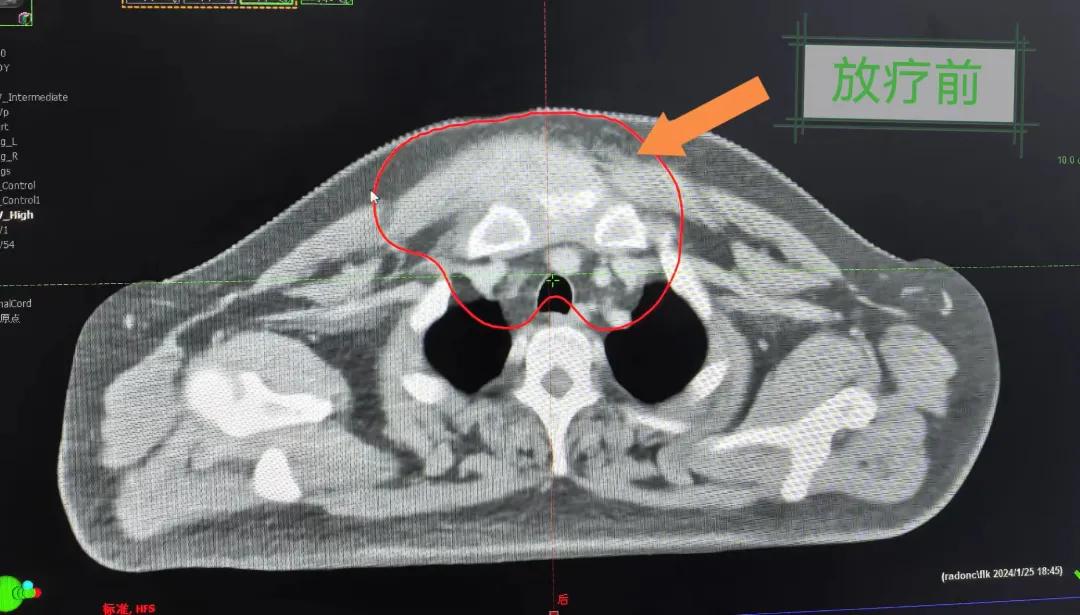

2個月前,市二院放療科接診了一名特殊的病人。一位40歲的中年男人,其前胸部竟然長了一個巨大的大腫塊,已有8cm左右且疼痛。

經(jīng)過詳細(xì)詢問病史,得知患者半年前前胸部突然出現(xiàn)一個腫塊,最初并未引起重視,以為只是普通囊腫,就隨便抹點藥,貼了膏藥。然而,腫塊并未縮小,反而逐漸增大,并伴隨著難以忍受的疼痛,嚴(yán)重影響了患者的日常生活和工作。隨后就診于當(dāng)?shù)蒯t(yī)院,行“胸部腫物穿刺活檢術(shù)”,術(shù)后病理提示為鱗狀細(xì)胞癌。突如其來的打擊讓患者不知所措,盡管嘗試了保守治療,但效果并不理想,僅能暫時緩解疼痛。

患者經(jīng)多方咨詢與打聽,在家屬的陪同下來到市二院放療科找到趙亮主任尋求幫助。入院后迅速完善了相關(guān)檢查,診斷為罕見的“胸壁腫瘤”。因腫瘤體積大,侵犯周圍組織,手術(shù)治療難度較大,經(jīng)院內(nèi)多學(xué)科會診后,決定采用無創(chuàng)的局部放射治療。在初步告知患者及家屬治療方案時,病人及家屬都擔(dān)心預(yù)后及放療可能引起的不適,趙亮主任詳細(xì)且耐心的向家屬和病人講述放療過程中可能出現(xiàn)的不良反應(yīng),確保讓他們安心治療。

隨后,趙亮主任帶領(lǐng)放療團隊以最快的速度完成了患者的放射治療計劃,在保證放療精準(zhǔn)打擊腫瘤的同時,利用先進的三維立體精確放療技術(shù),最大限度的避免心臟、肺部的損傷發(fā)生,整體治療精準(zhǔn)度達到1mm以內(nèi)。經(jīng)過10次的放射治療后,患者疼痛已明顯減輕,胸部腫物肉眼可見的縮小,患者及家屬臉上終于露出久違的笑臉。

治療期間,患者沒有出現(xiàn)明顯不適,治療結(jié)束后,患者胸壁腫物由最初8cm縮小至約1cm,后患者至外科行手術(shù)治療。